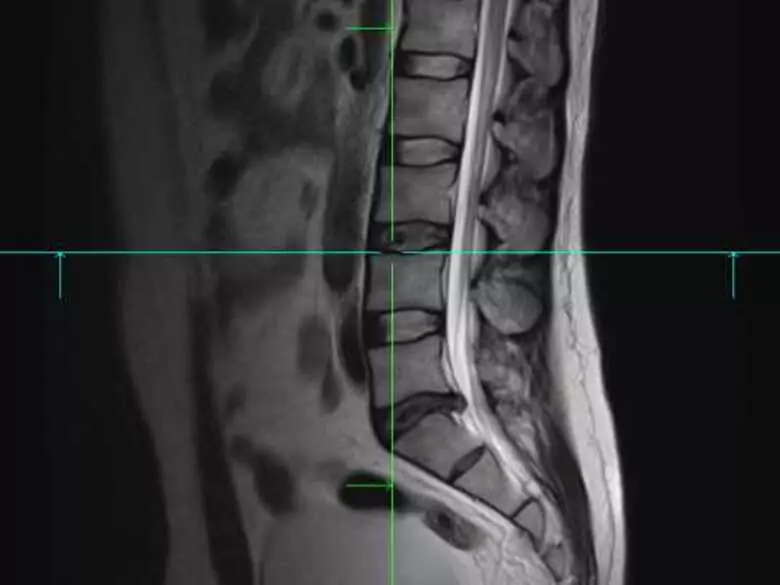

Dyskopatia to nic innego jak wypadnięcie krążka międzykręgowego z miejsca, jego naturalnego położenia. W większości przypadków, dyskopatie obejmują najczęściej dolny odcinek kręgosłupa (odcinek krzyżowy oraz lędźwiowy).

Dyskopatia